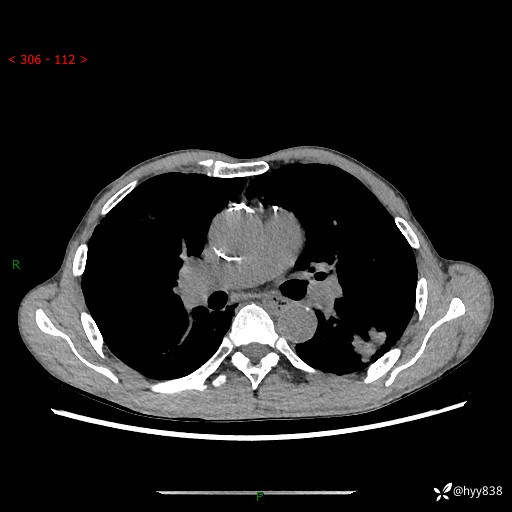

73岁/男,发现肺占位1月余。肺气肿背景,是否恶性倾向---结果公布~

现病史:患者于1月余前无明显诱因出现背部疼痛不适,无明显咳嗽、咳痰、胸闷、咯血、发热等不适,后于2024.5.3至当地市人民医院行胸部CT示:左肺下叶结块,大小约2.2cm*2.6cm,双肺多发小结节,双肺感染性病变,部分纤维增值灶,慢支并双肺局限性肺气肿,肺大泡,纵隔淋巴结增大并部分钙化,冠脉区及大血管壁钙化,双侧胸膜局限性增厚;后口服莫西沙星2周。2024.6.12复查胸部CT示:左肺下叶结块影形态较前饱满,较大截面范围约2.8cm*2.3cm,边缘可见细短毛刺及分叶,性质待查。现患者为求进一步诊治来我院,门诊以“肺占位”收入我科。 起病来,患者精神、食欲、睡眠尚可,大小便正常,体力体重轻微下降。

胸部CT平扫+增强

各期CT值:48hu 100hu 78hu